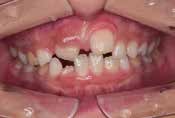

Before

After

上あごの成長が少なく、特に前歯のガタガタが目立っていました。口呼吸のクセや飲み込み方に良くないクセが確認されました。

治療を終えて

マイオブレイスとBB1装置で上あごの成長を助け、鼻呼吸や正しい飲み込み方を身につけることで、きれいな歯並びとしっかり噛めるお口に変わっていきました。

姿勢やお口の機能を正しく整えたので、後戻りしない綺麗な歯並びを維持できています。もちろん非抜歯です。

主訴・治療内容 当院と交流のある歯科医師の先生が、ご自身のお子さまの治療を任せてくださいました。

「難しい歯並びでも永久歯を抜かず、全身の健康と顔立ちも考えて治療してくれる」と信頼していただいて治療開始。

治療期間 3年

費用 462,000円(税込)